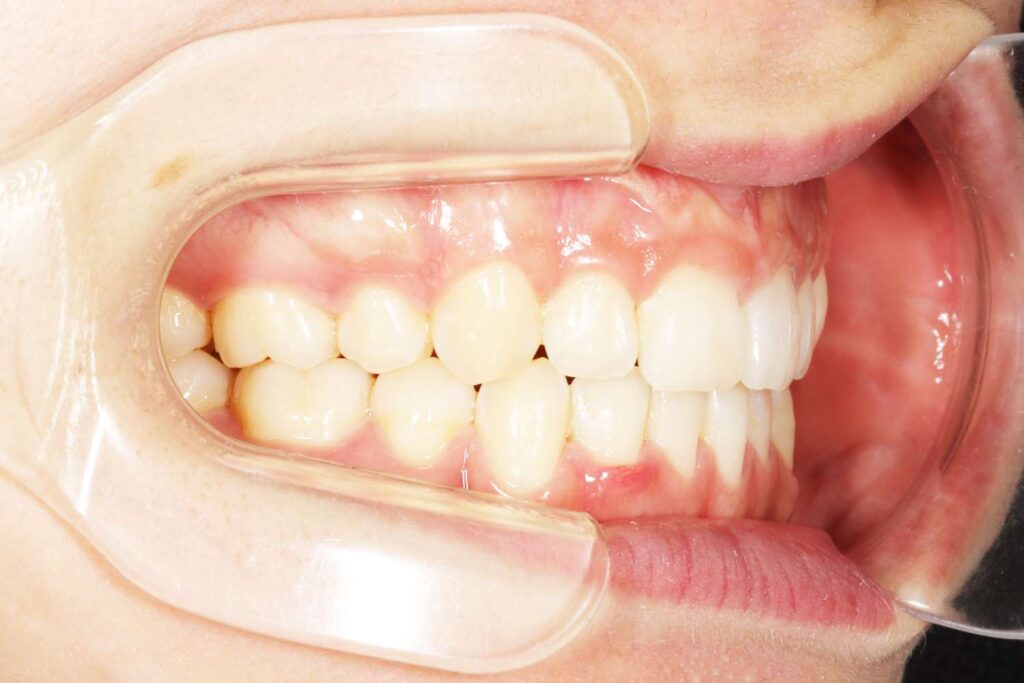

Before

年齢 10代

治療装置 表側の矯正装置(ホワイトコース)

治療内容 上下左右4本抜歯

治療期間 2年1か月

リスク 歯の移動に伴う痛み、歯肉退縮、歯根吸収、歯肉炎、虫歯

主訴 ガタガタが気になる

症状 叢生(ガタガタ)

治療回数 25回程度

総額費用 105万円程度